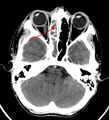

| يشير السهم إلى منطقة الالتهاب في جيوب الفك العلوي في الجانب الأيسر من الوجه. لاحظ أن المنطقة التى يشير لها السهم ليست شفافه لقلة الهواء فيها، مما يشير إلى امتلائها بالسوائل بالمقارنه مع الجانب الآخر من الوجه. | |